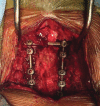

Successful arthrodesis at the craniocervical junction and atlantoaxial joint can be more challenging than in other segments of the cervical spine. Different techniques for spinal fixation in this region have been well described, along with auxiliary methods to improve fusion rates. The occipital vascularized bone graft is a novel technique that can be used to augment bony arthrodesis in the supra-axial cervical spine. It provides the benefits of a vascularized autologous graft, such as accelerated healing, earlier fusion, and increased strength. This technique can be learned with relative ease and may be particularly helpful in cases with high risk of nonunion or pseudoarthrosis in the upper cervical spine.